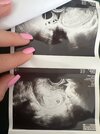

Hej dziewczyny, podłączę się pod ten post, bo troszkę wariuję. Będę bardzo wdzięczna za odpowiedź. Ostatnią miesiączkę miałam 5 lipca. Moja beta dzień przed miesiączka 3.08 wyniosła 134 (progesteron 54,03), 5.08 beta 288,3, 7.08 beta 695,6. Nie martwią mnie przyrosty, jednak byłam 7.08 u ginekolog (wiem, że to za wcześnie, ale przez wzgląd na tryb mojej pracy potrzebowałam zwolnienia) i był widoczny pęcherzyk wielkości 0,63mm, z tego co wiem to przy takich wartościach to nie powinno być nic widoczne. Wg okresu wychodził mi wczoraj (7.08) 4t5d, a wg tego pęcherzyka po usg 5t2d. Czy ten pęcherzyk nie jest za duży na ten etap? Doktor mimo wszystko zleciła mi branie progesteronu i acard, powiedziała, że martwi ją jakiś płyn i pytała czy nie mam plamień, a ich nie mam. Ciężko mi dokładnie powiedzieć o co chodziło, bo sama nie do końca to zrozumiałam. Czy któraś z was też tak miała? Czy jest się czym martwić? Próbuję wyluzować, ale chyba każda z nas wie jak jest z tym ciężko. Kolejne USG będę miała 18.08.

Załączniki

• image.jpg

image.jpg

1,2 MB · Wyświetleń: 112